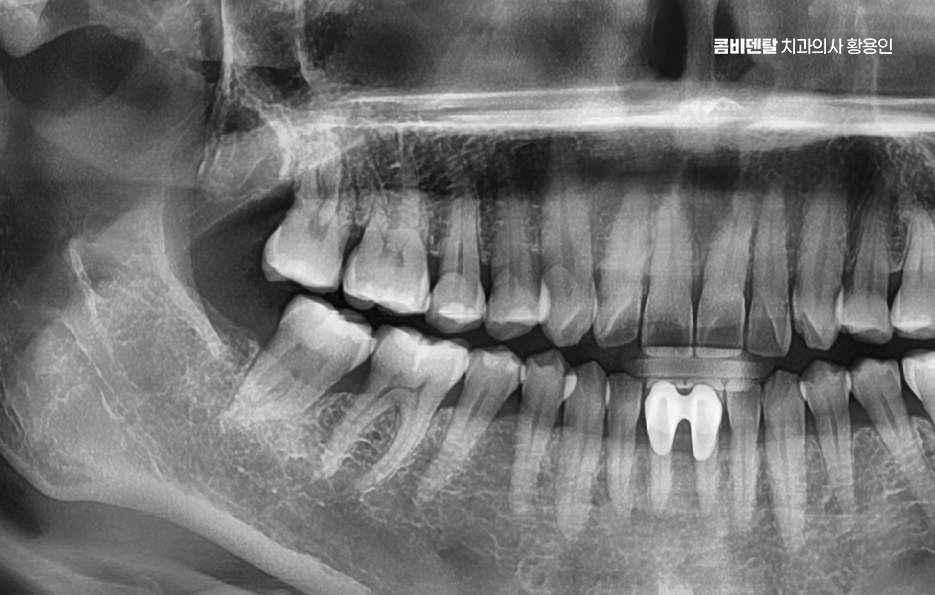

이런 경우에는 염증이 너무 심해지기 전에 빠르게 치과에 내원해서 사랑니 위치와 형태를 확인하는 X-ray 검사를 먼저 진행해야 하고 진단 결과 사랑니가 턱뼈에 수평으로 눌려 있거나, 인접 치아 뿌리를 밀고 있는 형태라면 단순히 약물치료만으로는 해결이 되지 않기 때문에, 염증을 가라앉히고 난 후 발치를 진행하는 방향으로 치료가 이루어지는 경우가 일반적이라 할 수 있어요

또 사랑니가 잇몸 안쪽에서 완전히 매복된 경우에도 사랑니 주변 잇몸 통증에 통증이 생기는 경우가 있는데 겉에서 보이지 않더라도 X-ray 상에서 보면 사랑니가 비스듬히 누워 있거나 옆 치아를 밀고 있는 경우가 많은데 이런 매복 사랑니는 염증이 없더라도 조용히 인접 치아의 뿌리를 괴사시키거나 인접면 충치를 유발하기도 해서 통증이 발생하지 않더라도 예방적 발치를 권유받는 경우도 있고 통증이 시작된 후에는 주변 뼈 흡수나 치주염, 잇몸 괴사로 진행될 가능성도 있기 때문에 사랑니 발치 판단을 적절히 세울 필요가 있어요

특히 성인 초반까지는 사랑니 뿌리가 완전히 자리 잡기 전이라 발치가 비교적 쉬운 편인데, 나이가 들수록 뿌리가 복잡하게 자라거나 신경관과 가까워져 발치 난이도도 높아지고 회복 기간도 길어지는 경향이 있어서 치통이 있든 없든, 사랑니의 위치와 방향은 미리 체크하고 치료 계획을 세워두는 것이 안전한 방법이라 할 거예요